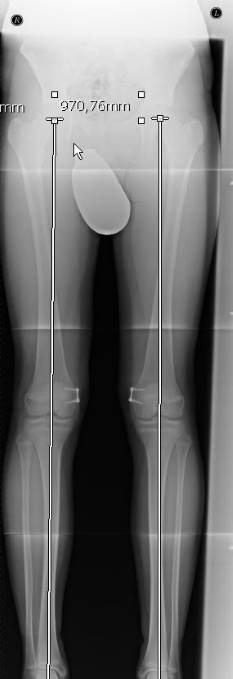

In einer Röntgenaufnahme des gesamten Beines kann der Arzt das Ausmaß der Abweichung von der Mitte des Kniegelenks genau bestimmen. Der Wert wird als MAD (mechanische Achsdeviation) in Millimetern angegeben. Zusätzlich wird der exakte Winkel der Achsabweichung ausgemessen.

Bei einer höhergradigen Achsfehlstellung, die nicht mehr nur durch das Alter des Kindes erklärbar ist, wird eine beidseitige Ganzbeinaufnahme im Röntgen angefertigt. So kann der Orthopäde sekundäre Ursachen ausschließen. Anhand des Röntgenbildes führt der Arzt eine Achsbestimmung und Winkelmessung durch. So kann er das Ausmaß und die Lokalisation der Beinachsenfehlstellung genau beurteilen. Erneute Röntgenaufnahmen können den Verlauf einer Beinachsenfehlstellung kontrollieren.

Um die mechanische Achsdeviation (MAD), also das genaue Ausmaß der Abweichung von der Mitte des Kniegelenks abzuschätzen, ermittelt der Kniespezialist die Mikulicz-Linie. Diese bestimmt er anhand der Röntgen-Ganzbeinaufnahme. Sie führt vom Zentrum des Hüftkopfes bis zur Mitte des oberen Sprunggelenks. Verläuft die Mikulicz-Linie nicht mittig durch das Kniegelenk, sondern durch die Innenseite, handelt es sich um eine Varusfehlstellung (O-Bein). Verläuft sie durch die Außenseite des Kniegelenks, liegt eine Valgusfehlstellung (X-Bein) vor. Zusätzlich wird der exakte Winkel der Achsabweichung ausgemessen.

Zur Einschätzung der Beinachsenfehlstellung wird die Ganzbein-Röntgenaufnahme des Kniegelenks von vorne in 4 Quadranten eingeteilt. Verläuft die Mikulicz-Linie und somit die mechanische Beinachse innerhalb der beiden mittleren Quadranten, liegt eine normale bzw. geringgradig abweichende Beinachse vor, die nicht operativ korrigiert werden muss. Verläuft die Beinachse außerhalb der inneren Quadranten, liegt eine pathologische (krankhafte) Beinachse vor.